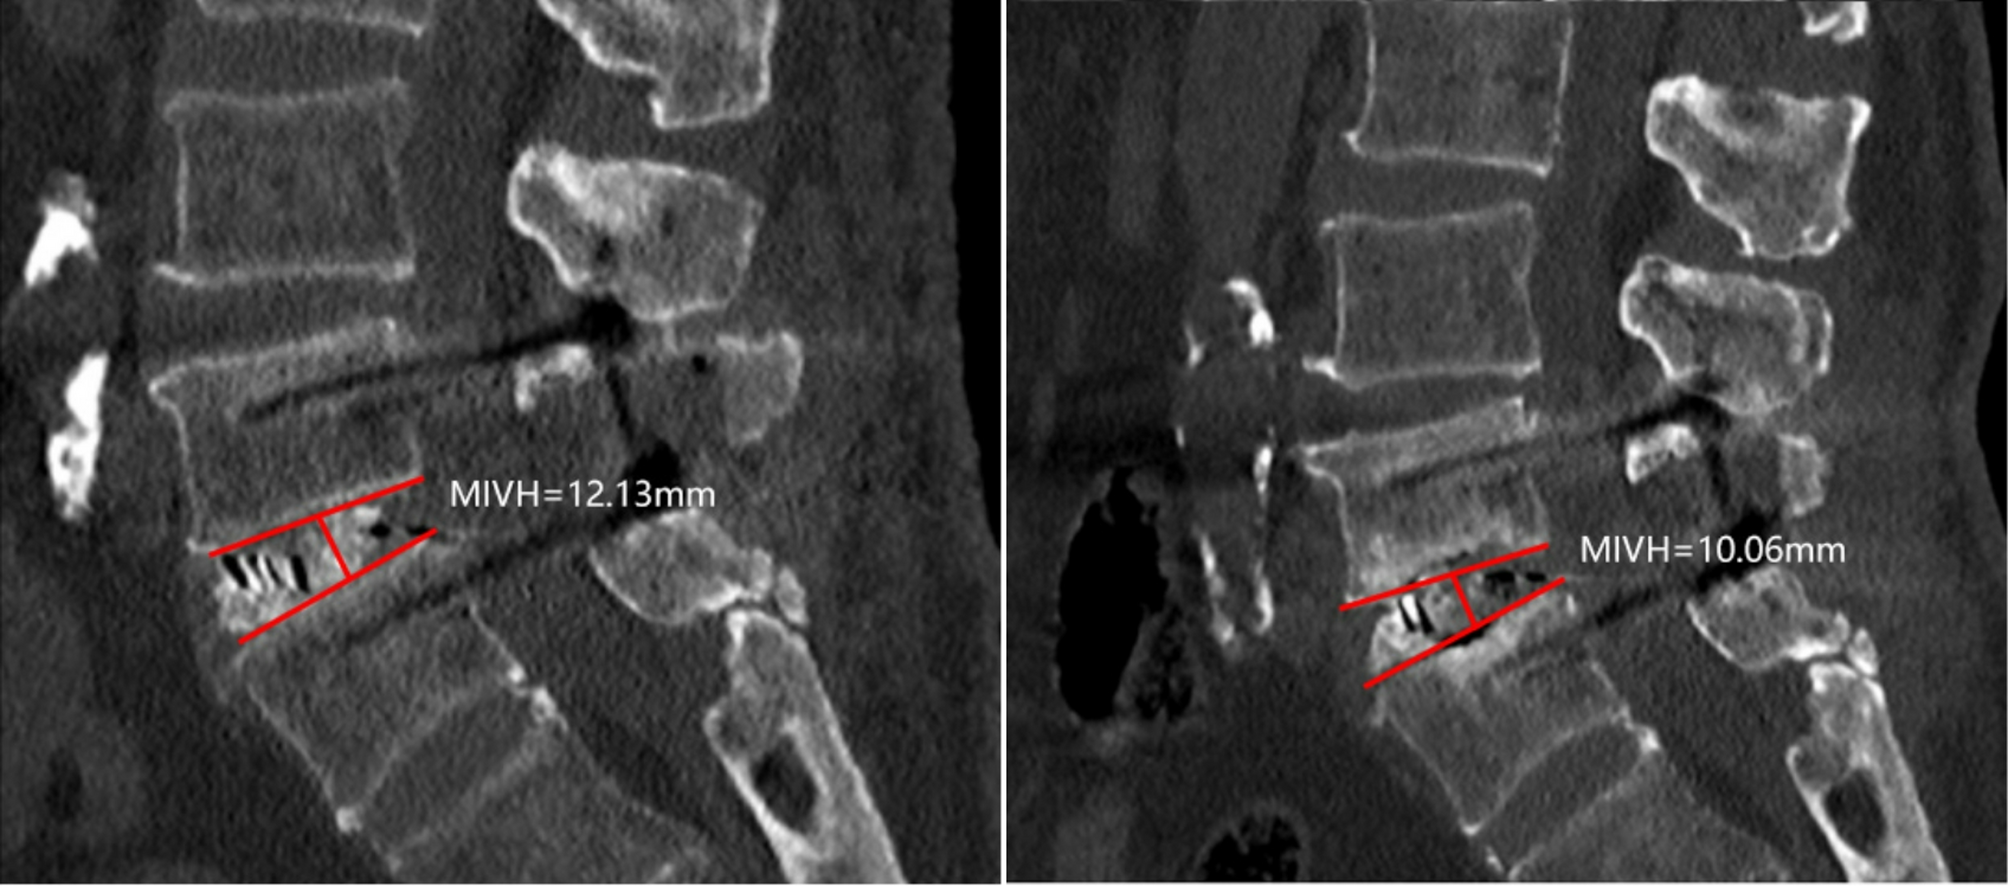

An example of measuring cage subsidence.